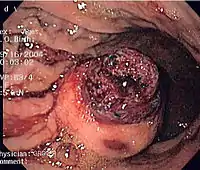

| Histopathologic image of gastrointestinal stromal tumor of the stomach. Hematoxylin-eosin stain. | |